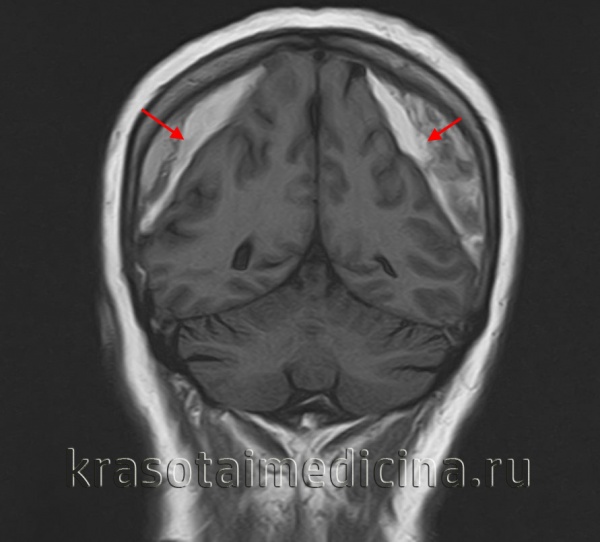

Решающими методами в диагностике субдуральной гематомы являются КТ и МРТ головного мозга. В диагностике острых гематом предпочтение отдается КТ головного мозга, которая в таких случаях выявляет однородную зону повышенной плотности, имеющую серповидную форму. С течением времени происходит разуплотнение гематомы и распад кровяных пигментов, в связи с чем через 1-6 нед. она перестает отличается по плотности от окружающих тканей. В подобной ситуации диагноз основывается на смещении латеральный отделов мозга в медиальном направлении и признаках сдавления бокового желудочка.

При проведении МРТ может наблюдаться пониженная контрастность зоны острой гематомы; хронические субдуральные гематомы, как правило, отличаются гиперинтенсивностью в Т2 режиме. В затруднительных случаях помогает МРТ с контрастированием. Интенсивное накопление контраста капсулой гематомы позволяет дифференцировать ее от арахноидальной кисты или субдуральной гигромы.